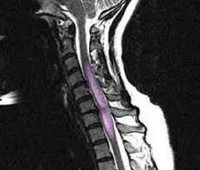

Сирингомиелия (греч. syrinx - тростник, пустая дудка; myelon - спинной мозг) - хроническое дизэмбриогенетическое заболевание, характеризующееся появлением полостей в сером веществе шейных или грудных сегментов спинного мозга и нередко - в продолговатом мозге (сирингобульбия).

Сирингомиелия

Чаще всего полости формируются в области задних рогов спинного мозга с воздействием на чувствительные нейроны. Пациенты ощущают упорные тупые ноющие боли в соответствующих дерматомах и склеротомах (в шее, плечевом поясе, верхней конечности, между лопаток, в грудной клетке). Нередко поводом для обращения к врачу являются безболезненные ожоги кожи верхней конечности или туловища. При прогрессировании заболевания развиваются атрофические парезы соответствующих миотомов и нейротрофические расстройства с остеопорозом и деформацией костей и суставов (плечевых, локтевых, межфаланговых на кисти). В неврологическом статусе выявляется сегментарная диссоциированная анестезия с выпадением болевой и температурной чувствительности, сохранностью тактильного и проприоцептивного чувства. Часто зона нарушенной чувствительности имеет вид симметричной или асимметричной куртки (полукуртки) и захватывает надплечье и верхнюю часть спины. Глубокие рефлексы, замыкающиеся на уровне пораженных сегментов спинного мозга, угасают. Однако мышечная сила длительно сохраняется. Только в тех случаях, когда полость захватывает и передний рог спинного мозга, развиваются вялые парезы и атрофии мышц. В нижних конечностях обычно определяется гиперрефлексия и другие знаки поражения пирамидной системы, включая симптом Бабинского. Пирамидная система частично страдает на уровне имеющейся полости в заднем роге спинного мозга или в центромедуллярной области при резком расширении центрального спинномозгового канала. Сегментарная анестезия в таких случаях бывает симметричной и двухсторонней (нарушается функция проводников передней спайки, где перекрещиваются аксоны чувствительных клеток задних рогов. Иногда развивается массивное утолщение кисти - хейромегалия, что связано с поражением вегетативных клеток бокового рога верхних грудных сегментов. Кожа сухая, исчезает ее гладкость. Атрофии распространяются на длинные мышцы спины, что проявляется сколиозом или кифосколиозом.

Является врожденным дефектом развития глии, которая патологически размножается (глиоматоз) с последующим ее распадом и формированием полости в сером веществе сегментов спинного мозга. Сохраняющиеся по периферии такой полости клетки глии сецернируют жидкость, которая постепенно приводит к расширению этой полости и дегенеративному разрушению прилежащих к этой полости нейронов (чувствительных нейронов заднего рога, мотонейронов переднего рога спинного мозга). Истинная сирингомиелия нередко сочетается с другими дизрафическими изменениями скелета и мягких тканей: сколиоз и сглаженность грудного кифоза позвоночника, высокое небо, неправильные ряды зубов, диспластическое строение лицевого черепа, ушных раковин, шестипалость, асимметрия сосков молочной железы, добавочные рудиментарные соски, раздвоенные подбородок и кончик языка В эбриогенезе дефектным оказывается и спинной мозг, глиозная ткань которого участками недостаточно дифференцировалась. В процессе онтогенеза в результате провоцирующих факторов таких как травма, инфекционное заболевание и , эта глиозная ткань подвергается отмеченному выше патологическому развитию с формированием полостей. Однако такая «истинная» сирингомиелия встречается редко. Гораздо чаще (в 2/3 случаев) сирингомиелия сопутствует аномалиям кранио-вертебрального стыка (аномалия Арнольда-Киари с опущением миндалины мозжечка, базилярная импрессия, платибазия, ассимиляция атланта, аномалия Клиппеля-Фейля ). При таких аномалиях обычно расширяется центральный спинномозговой канал (гидромиелия), который на уровне отдельных сегментов спинного мозга может аневризматически расширяться и разрушать серое вещество этих сегментов с соответствующими клиническими проявлениями. Сирингомиелические полости могут формироваться после тяжелой травмы позвоночника и спинного мозга с гематомиелией, а также при инфаркте спинного мозга (некротическая киста). При истинной сирингомиелии болезнь постепенно прогрессирует.